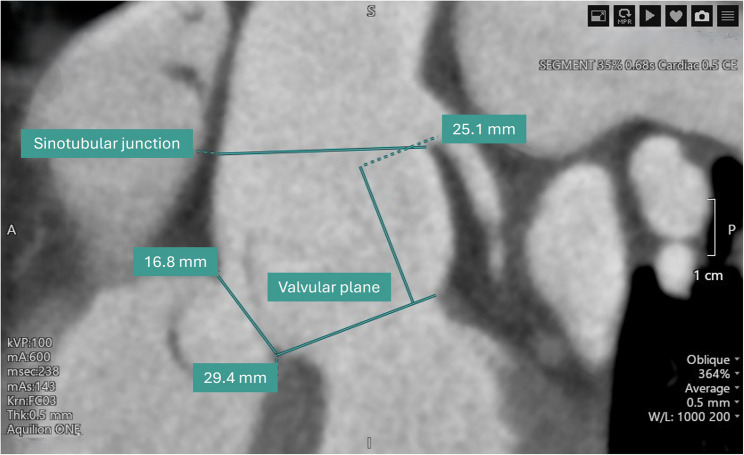

35岁男性,无明显心血管病史,心悸复发。最初的超声心动图评估显示偏心左心室肥厚,轻度收缩功能障碍,怀疑室间隔缺损,二尖瓣主动脉瓣和右心室扩张。经食管超声心动图显示右冠状窦动脉瘤样扩张伴主动脉-心房/心室瘘,经增强计算机断层血管造影进一步证实。冠状动脉造影发现单冠状动脉异常,左冠状动脉占优势,右冠状动脉缺失。手术修复成功关闭瘘,术后主动脉返流轻微。随访一年,心脏尺寸和功能恢复正常,主动脉瓣返流稳定。基因测序未发现可识别的突变。由于与二尖瓣主动脉瓣和冠状动脉异常相关的并发症的潜在风险,建议定期监测。

A 35-year-old male, without significant cardiovascular history, presented with recurrent palpitations. Initial echocardiographic evaluation demonstrated eccentric left ventricular hypertrophy, mild systolic dysfunction, suspicion of a ventricular septal defect, bicuspid aortic valve, and right ventricular dilation. Transesophageal echocardiography revealed an aneurysmal dilation of the right coronary sinus with an aorto-atrial/ventricular fistula, further confirmed by contrast-enhanced computed tomography angiography. Coronary angiography identified a single anomalous coronary artery with left dominance and absence of the right coronary artery. Surgical repair successfully closed the fistula, with mild post-operative aortic regurgitation. Follow-up at one year indicated normalization of cardiac dimensions and function, with stable moderate aortic valve regurgitation. Genetic sequencing found no identifiable mutations. Regular monitoring was recommended due to the potential risk of complications related to the bicuspid aortic valve and coronary anomaly.